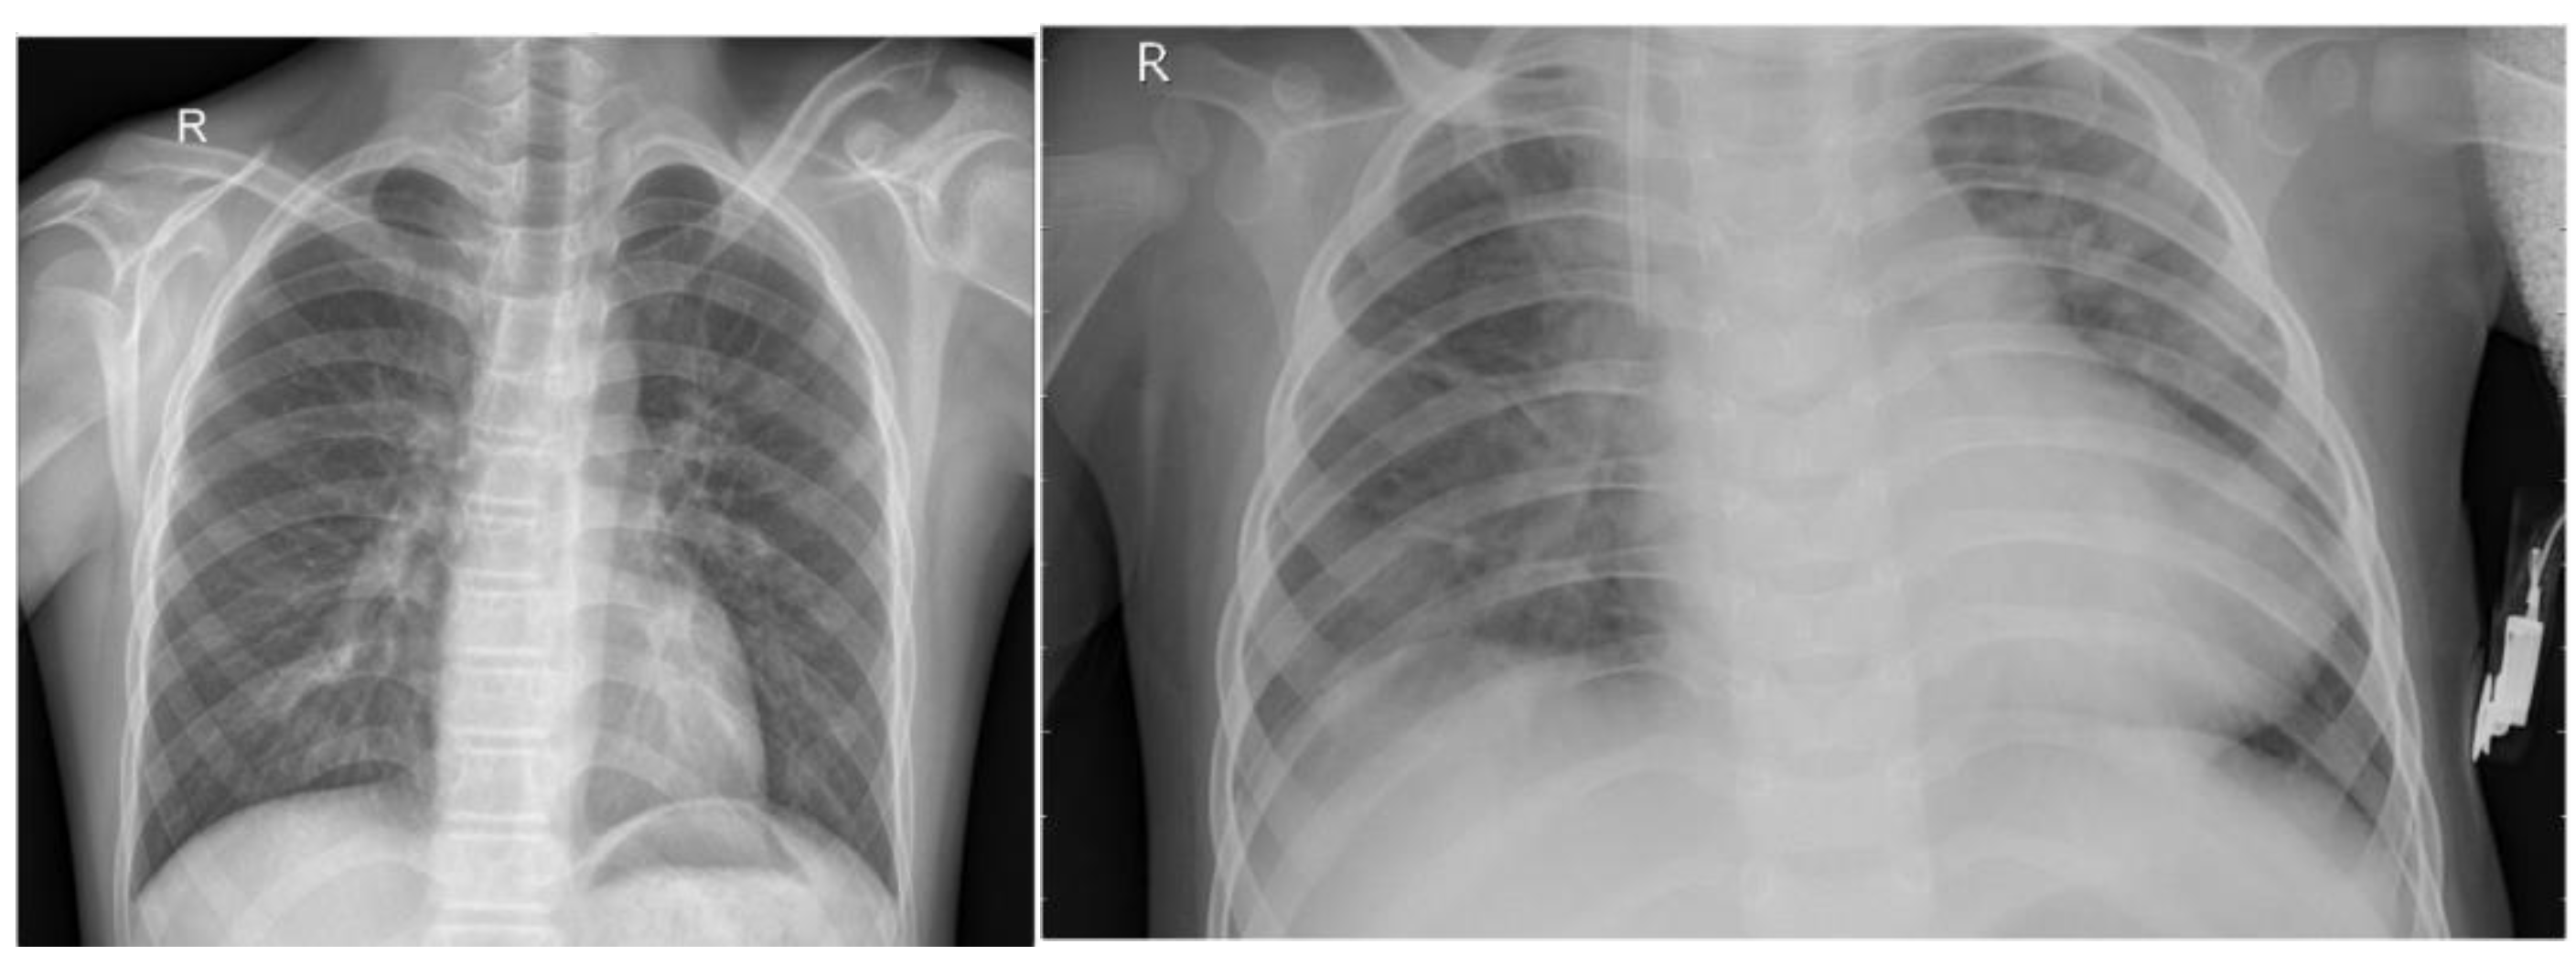

4.1. Dataset

4.2. Comparison and Analysis of Results